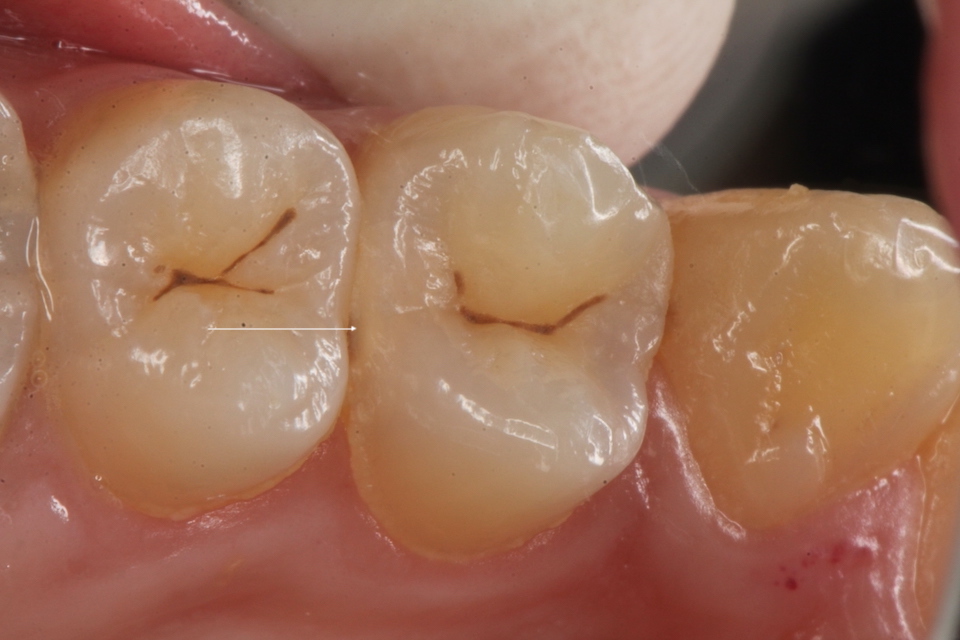

下顎7番の頬側歯茎部カリエスの原因 2025.06.04